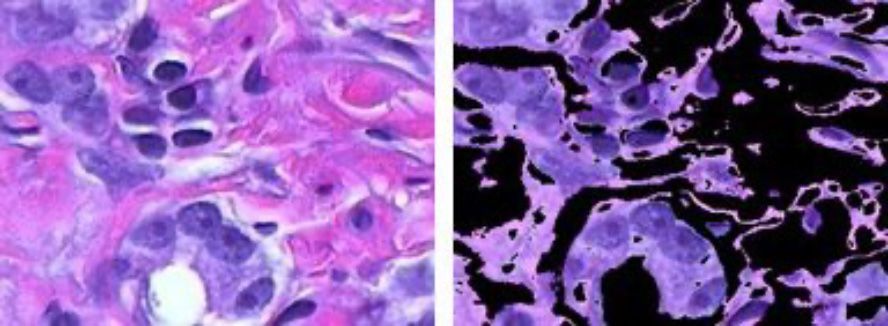

k-평균 군집화를 사용한 색 기반 영상 분할.